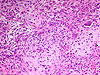

CASO N° 2 (Dr. Elismauro e Dr. Delgado)

Paciente do gênero masculino, 85 anos de idade, apresenta um aumento de volume na maxila esquerda.